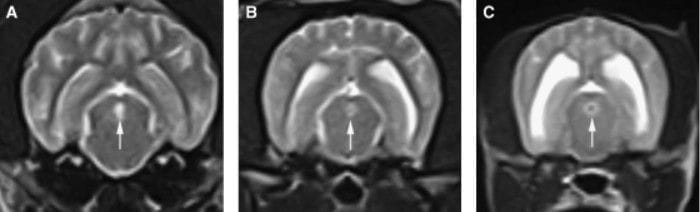

Transverse, spin echo T2-weighted MR images of the mesencephalon of three different small-breed dogs depicting no cerebrospinal fluid (CSF)signal-void sign (A), an intermediate-intensity CSF signal-void sign (B), and a pronounced CSF signal-void sign (C) in the mesencephalic aqueduct (arrow). Forthe statistical analyses, both the intermediate CSF signal-void sign and pronounced CSF signal-void sign were considered as definitively detected